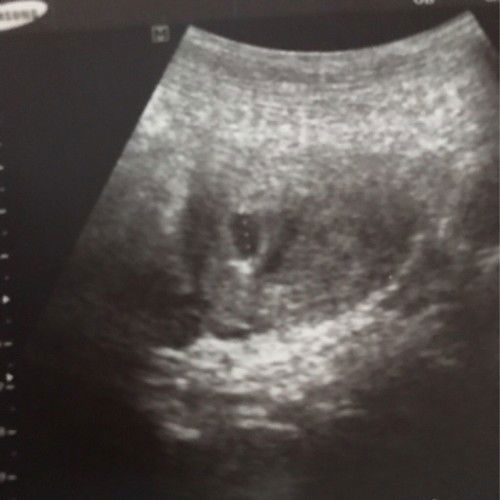

ada spotting 20hb hosp kata misccariage..22hb check up doktor kta kantung membesar..tunggu 2minggu untuk scan lagi sekali..baru 6week..x ada bleeding..lendir darah pada 20hb jek tu pun sikit jek..lpas tu x ada..klau penat bru kluar lendir coklat tu pun sikit jek..klau bedrest x ada kluar spotting..rasa putus harapan bila hosp ckp mcm tu..masih ada harapan ke?? #ttc5y #secondbaby